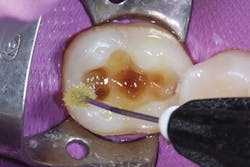

The selective etching technique was chosen, and 37% phosphoric acid (Total Etch, Ivoclar Vivadent) was applied for 30 seconds. The tooth was irrigated with water spray and air-dried (figure 2). Next, a universal bonding agent (Adhese Universal, Ivoclar Vivadent) was scrubbed on the cavity surface until an immobile layer was achieved (figure 3). The excess solvent was removed with an air stream for 20 seconds, and the adhesive was light cured for 10 seconds with an LED light (Bluephase Style, Ivoclar Vivadent) 1 mm away from the cavity.